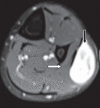

Results: The mean age of the eight patients was 40 (range 27-57) years. The most common presenting feature was a palpable mass. The mean interval between surgical treatment and the onset of clinical symptoms was 17.1 (range 4-72) months. Six of the eight tumours (75.0%) were located in the lower limb, while 2 (25.0%) were located in the upper limb. None of the patients had any preoperative neurological deficits. Tinel's sign was present in one patient. Magnetic resonance (MR) imaging showed that the findings of split-fat sign, low signal margin and fascicular sign were present in all patients. The entry and exit sign was observed in 4 (50.0%) patients, a hyperintense rim was observed in 7 (87.5%) patients and the target sign was observed in 5 (62.5%) patients. All patients underwent microsurgical excision of the tumour and none developed any postoperative neurological deficits.

Conclusion: Intramuscular schwannomas demonstrate the findings of split-fat sign, low signal margin and fascicular sign on MR imaging. These findings are useful for the radiological diagnosis of intramuscular schwannoma.